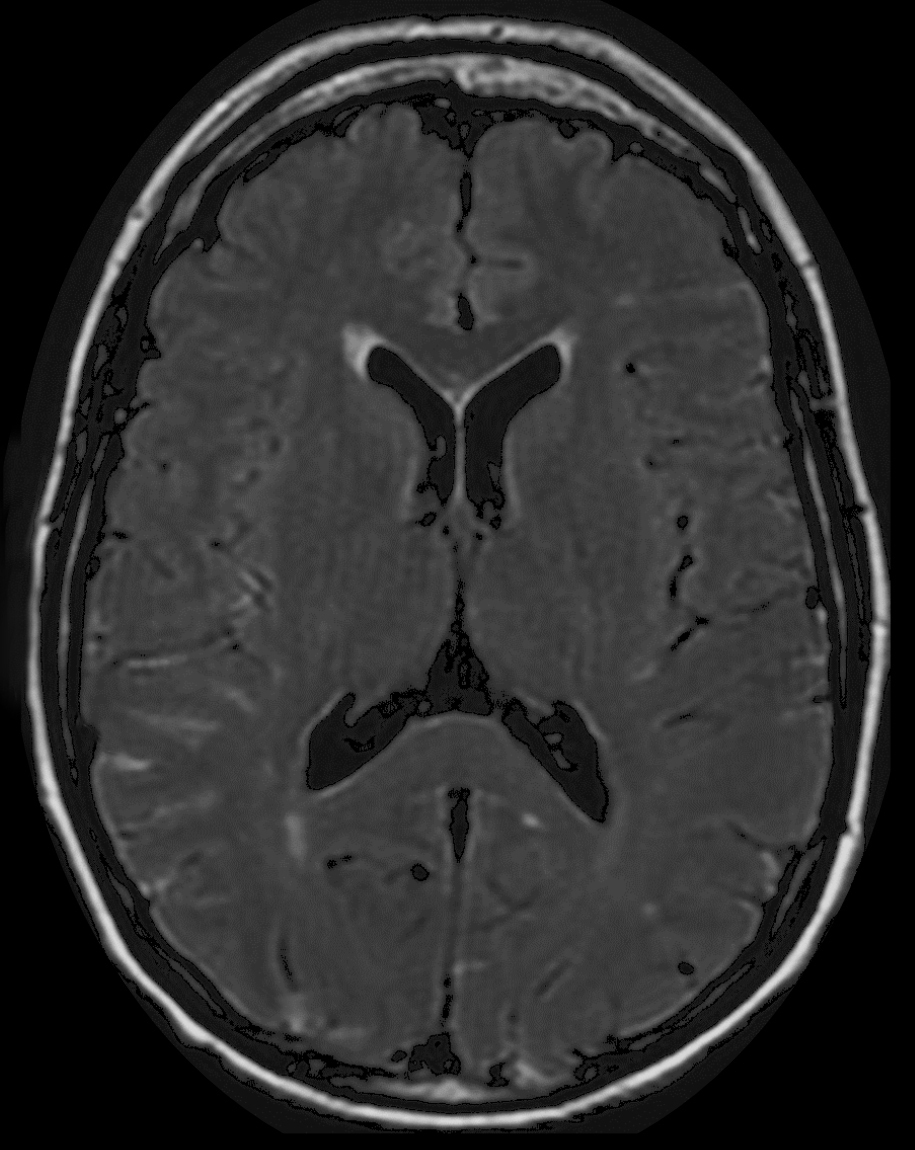

Quel est votre diagnostic ?

Il s'agit d’une IRM cérébrale en séquence FLAIR montrant des hypersignaux linéaires des espaces sousarachnoïdiens (flèches), l’hyperdensité de ces espaces signant l’hémorragie méningée. L’imagerie cérébrale occupe une place centrale dans le diagnostic initial, le suivi et le traitement des patients atteints d’hémorragie méningée. Un scanner doit être réalisé en urgence, il démontre une hyperdensité des espaces sousarachnoïdiens, évalue la sévérité par l’échelle de Fisher et recherche les complications précoces. Si l’IRM est accessible et que l’état du patient est compatible, les séquences FLAIR, T2* ou imagerie pondérée en susceptibilité magnétique (SWI) peuvent remplacer le scanner cérébral sans injection, avec une sensibilité plus élevée pour le diagnostic d’hémorragie méningée.